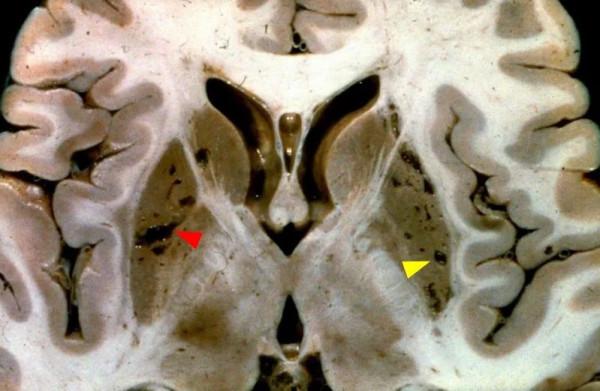

在大體標本上對照觀察腔梗灶(紅箭頭)與擴大的VR腔隙(黃箭頭)。